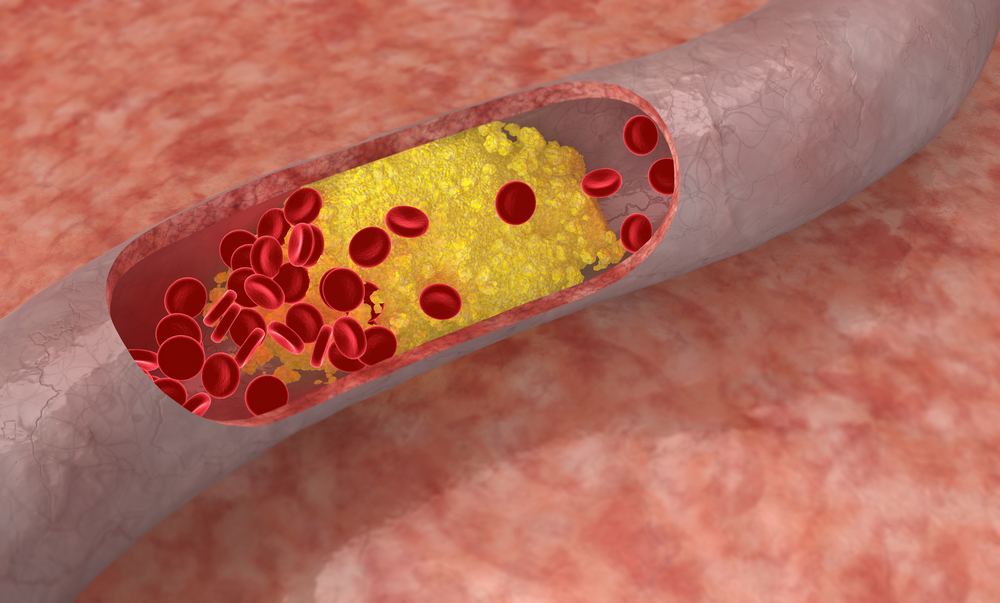

Холестерин в организме: влияние и функции (схемы и диаграммы)